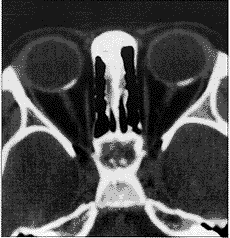

1994年12月18日,随诊检查1例3岁调节性内斜视日本女童时,发现双侧脉络膜病变,除血清肌酸磷酸酶升高外,其病史无特殊。每只眼均可见1个扁平黄色脉络膜病变(图1)。荧光血管造影检查显示两眼病变在早期呈低荧光,晚期呈高荧光(图2)。由于阻塞,吲哚花青绿血管造影检查,早期显示低荧光,晚期发生病变染色(图3)。超声检查(A超和B超)显示双侧明显的脉络膜病变,有高的内反射,符合钙化。计算机断层扫描显示双眼内有钙质沉积(图4)。在T1权重的核磁共振图像显示病变被钆(gadolinium)轻度增强。根据这些发现,诊断为脉络膜骨瘤。约2年后,双眼病变明显增大(图5),由荧光素和吲哚绿血管造影检查所确定。此时,双眼矫正视力仍为20/30,没有弱视的征象。对患者进行随诊,对肿瘤未予治疗。

图4 双眼计算机断层扫描

评 论 脉络膜骨瘤是脉络膜的一种良性骨性肿瘤,典型地见于10多岁至20多岁健康年轻女性。约25%的患者中,这种异常为双侧性1,2。此肿瘤一般发展并不快2~4。计算机断层扫描检查及A超和B超检查显示该肿瘤是一典型的脉络膜骨瘤。但是,此肿瘤的迅速增大是个例外。该肿瘤是在检查斜视时意外地被发现;与其它报告相比,这些早期肿瘤很小,而且患者很年轻。据我们所知,这是所报告的有此情况的最年轻患者。我们认为发生在小年龄的骨瘤可迅速增大。